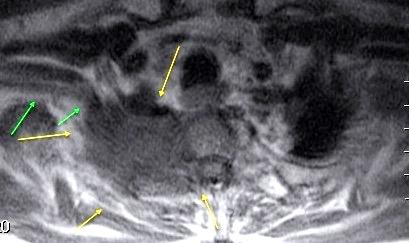

Empiema pleural izquierdo. Absceso del LID. Espondilodiscitis D11-D12.

Potsios C et al. Pyogenic Spondylodiscitis due to Streptococcus constellatus in an Immunocompromised Male Patient: A case Report and Review of the Literature. Case Reports in Infectious Diseases. 2019